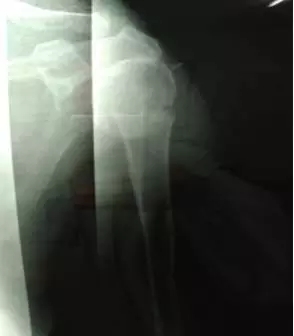

整復(fù)后復(fù)查X線片,骨折端位置良好。

鮑阿婆及家人看過片子后也十分滿意,“都說廣安醫(yī)院醫(yī)生的技術(shù)真是好,早知道3年前右手骨折在你們這里看,就不用吃那么多苦了”。鮑阿婆表示。

整復(fù)后